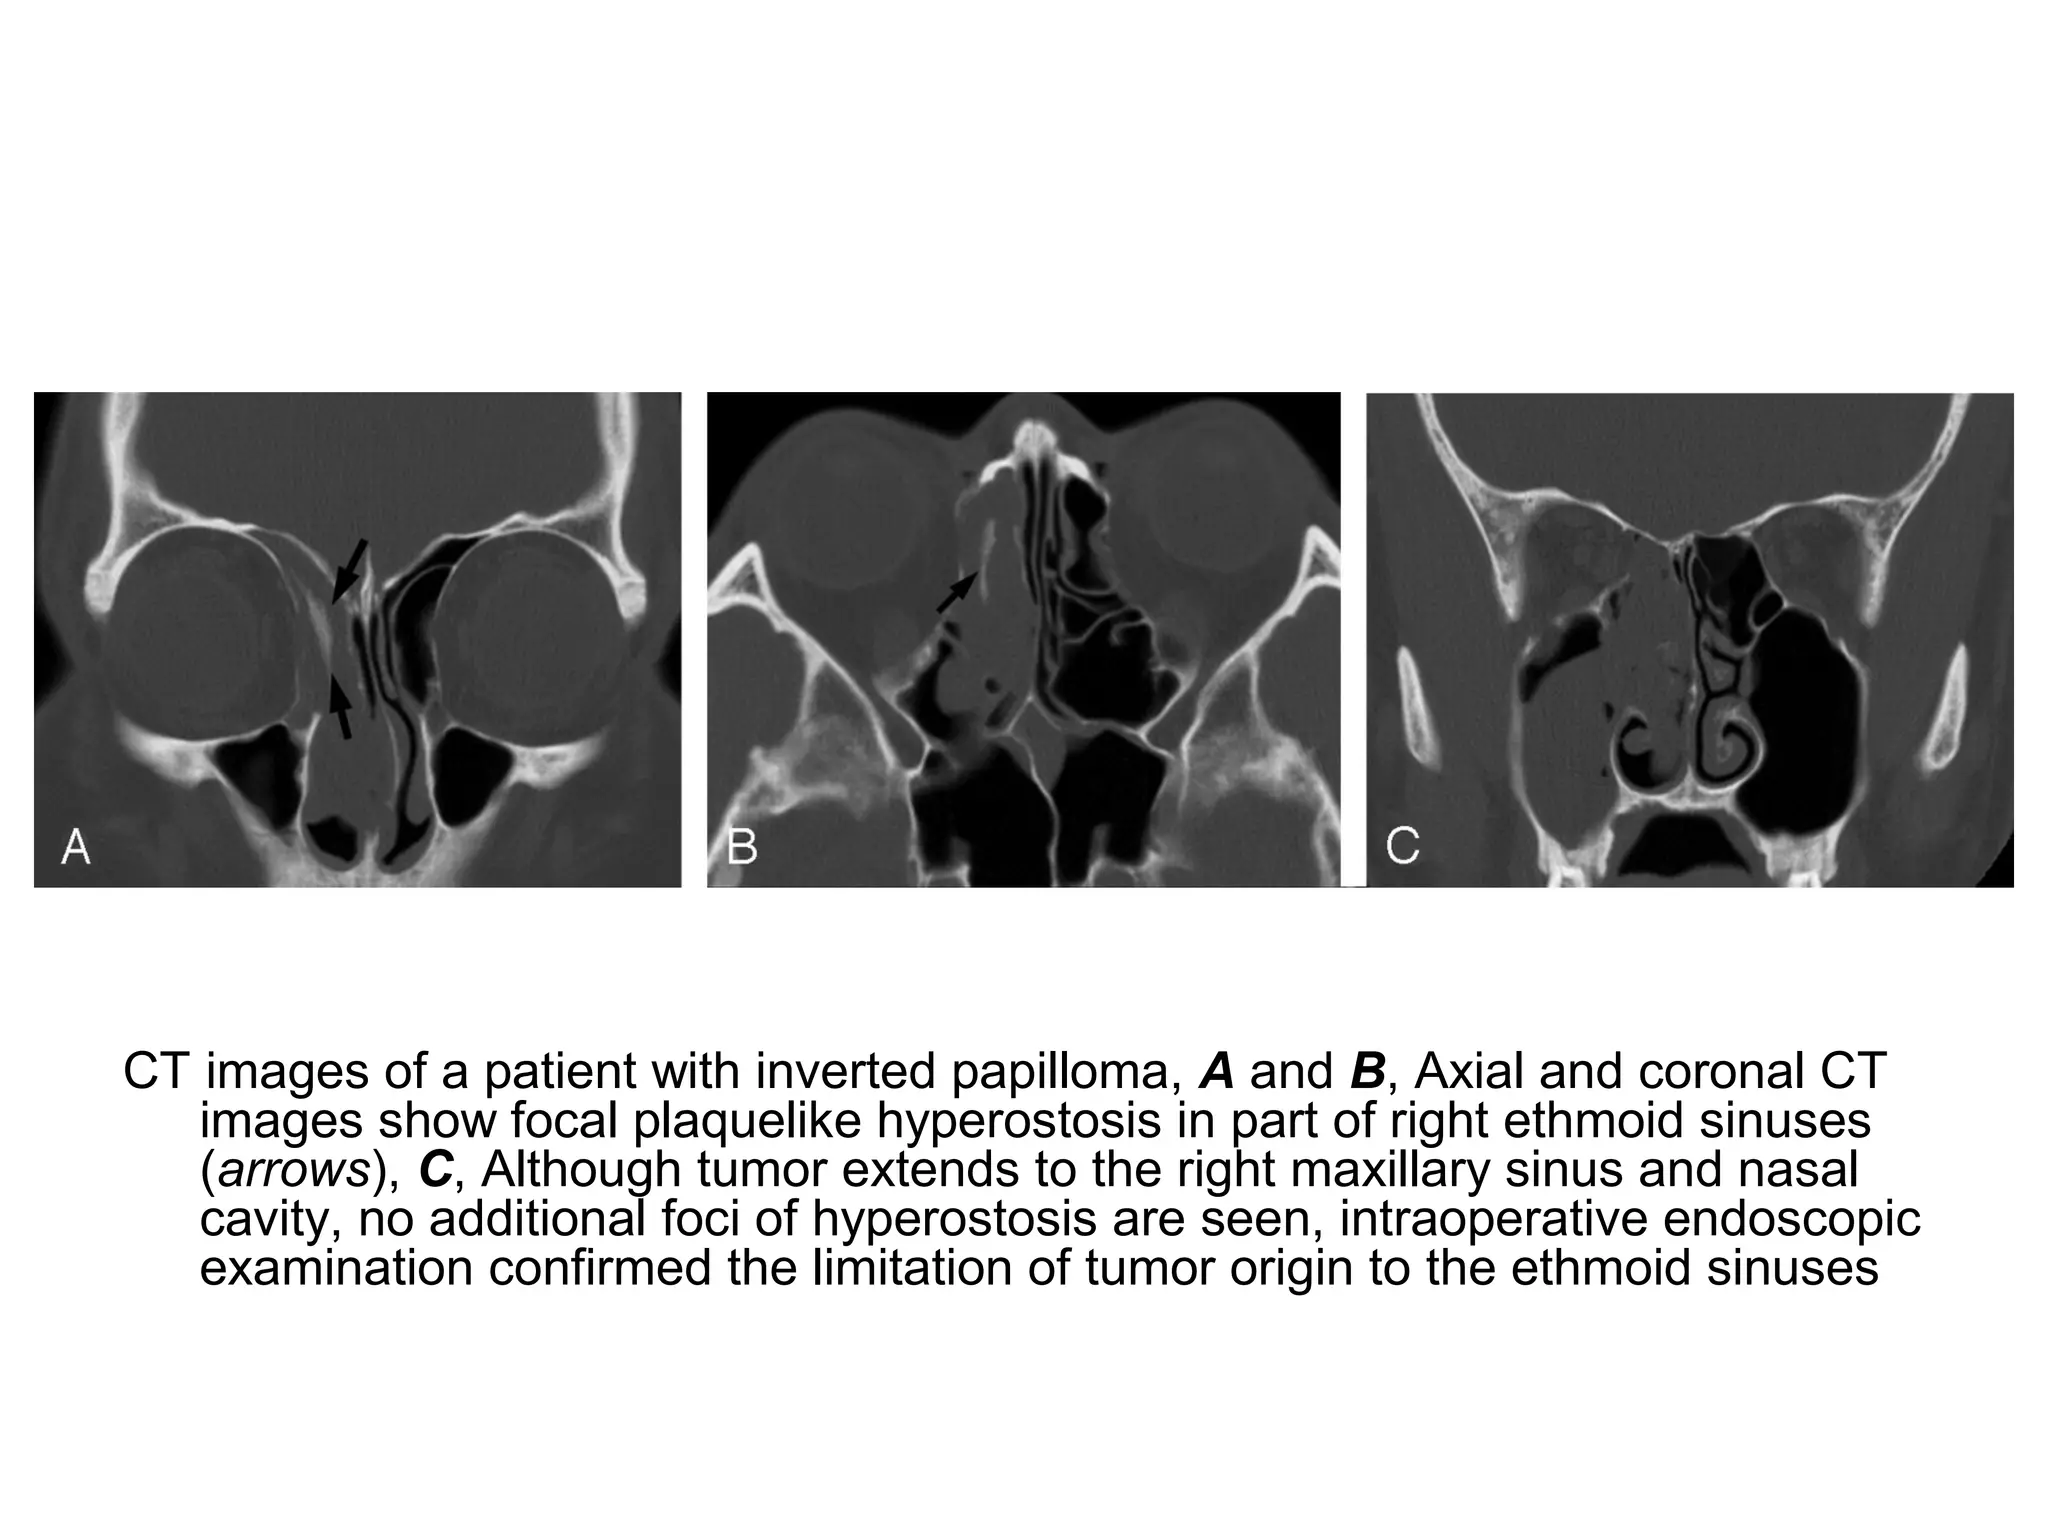

CT images of a patient with inverted papilloma, A and B, Axial and coronal CT

images show focal plaquelike hyperostosis in part of right ethmoid sinuses

(arrows), C, Although tumor extends to the right maxillary sinus and nasal

cavity, no additional foci of hyperostosis are seen, intraoperative endoscopic

examination confirmed the limitation of tumor origin to the ethmoid sinuses